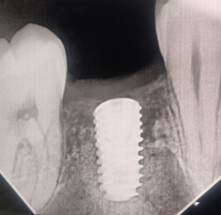

Приживление искусственных зубных конструкций является очень высоким и составляет 95-98%. На успешность операции по установке и дальнейшему заживлению влияют несколько факторов: Качество имплантата и надежность производителя. Чаще всего имплантаты изготавливают из биосовместимого, гипоаллергенного материала - титана. Он не отторгается организмом и через 2-3 недели после имплантации костная ткань срастается с имплантатом. Компетентность и опыт врача-имплантолога. Некоторые врачи могут допускать ошибки, которые будут стоить пациенту существенных моральных и финансовых убытков. Среди таких ошибок: - Недостаточное уделенное внимание к изучению анализов и анамнеза пациента относительно хронических болезней и аллергических реакций (здесь пациент должен быть максимально откровенным с врачом, ведь эта информация очень важна для разработки плана лечения), а также поверхностная диагностика состояния ротовой полости, мягких тканей и состояния кости. - Ошибки при выборе импланта, ведь они отличаются не только по производителю и цене, а по длине, диаметру, резьбе и конструкции в целом. - Проведение операции при недостаточном количестве костной ткани. В случаях, когда длительное отсутствие зуба привело к атрофии челюсти, пациенту понадобится пластика кости (синус-лифтинг). В целом мы рекомендуем пациентам не затягивать с имплантацией после удаления зубов, ведь через год кость рассасывается на 25%, затем за каждый последующий год процесс атрофии прогрессирует на 4%. Следовательно, как правило, если после удаления зуба прошло несколько лет, перед имплантацией врач должен провести процедуру по наращиванию костной ткани. - Погрешности в процессе вживления стержня. Например, неправильно подобранное место или угол вживления. Ответственность пациента. По статистике большинство случаев отторжения импланта фиксируются из-за несоблюдения пациентом рекомендаций врача. В частности, для успешного заживления в послеоперационный период пациенту необходимо: - Добросовестно принимать назначенные врачом препараты. - После каждого приема пищи полоскать рот растворами антисептиков. - На 3 недели отказаться от алкоголя, курения, посещения саун. - Не игнорировать плановые консультации у врача для контроля процесса приживления.

ВАЖНО! В нашей клинике человеческий фактор полностью нивелируется посредством навигационной хирургии и использованием цифрового протокола лечения. Этот протокол предусматривает сбор и анализ рентгеновских снимков и моделей полости рта пациента с переводом этих данных в цифровой вид. Это позволяет планировать реализацию постановки импланта и вид будущей коронки еще до этапа имплантации.